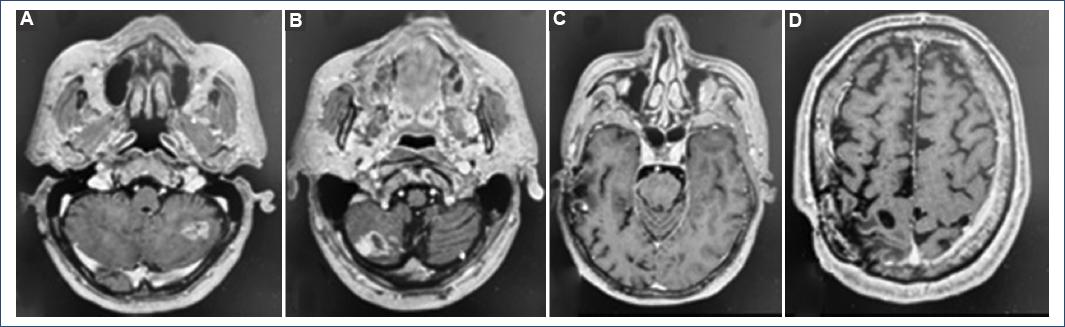

A 68-year-old male with no significant history who presents with a 1 week of evolution characterized by holocranial headache, decreased strength of the left hemibody (3/5), and epileptic seizures of focal onset that are secondarily generalized is admitted through the emergency room to the central military hospital. Treatment is started with levetiracetam 1000 mg every 12 h. Computed axial tomography and cerebral magnetic resonance imaging studies were done, which showed 6 supra and infratentorial intracranial lesions of heterogeneous intensity with enhancement ring contrast (Fig. 1).

Figure 1 Pre-operative magnetic resonance imaging in the T1 sequence in the axial section A: right frontoparietal lesion of heterogeneous intensity with ring contrast enhancement. B: left frontal lesion. C: right temporal lesion. D: lesion in the left cerebellar hemisphere. E: lesion in the hemisphere right cerebellar and left cerebellar peduncle.